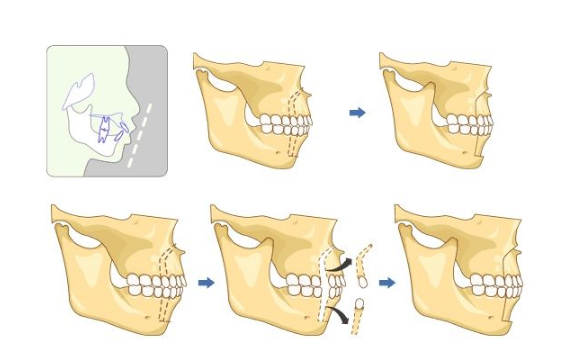

牙顎畸形圖片

牙槽骨突出

牙槽骨突出

牙槽骨突出

牙槽骨突出

牙槽骨突出

牙槽骨突出

牙槽骨突出

牙槽骨突出

牙槽骨突出

牙槽骨突出

牙槽骨突出

牙槽骨突出

牙槽骨突出

牙槽骨突出

牙槽骨突出

牙槽骨突出

牙槽骨突出

牙槽骨突出

牙槽骨突出

牙槽骨突出